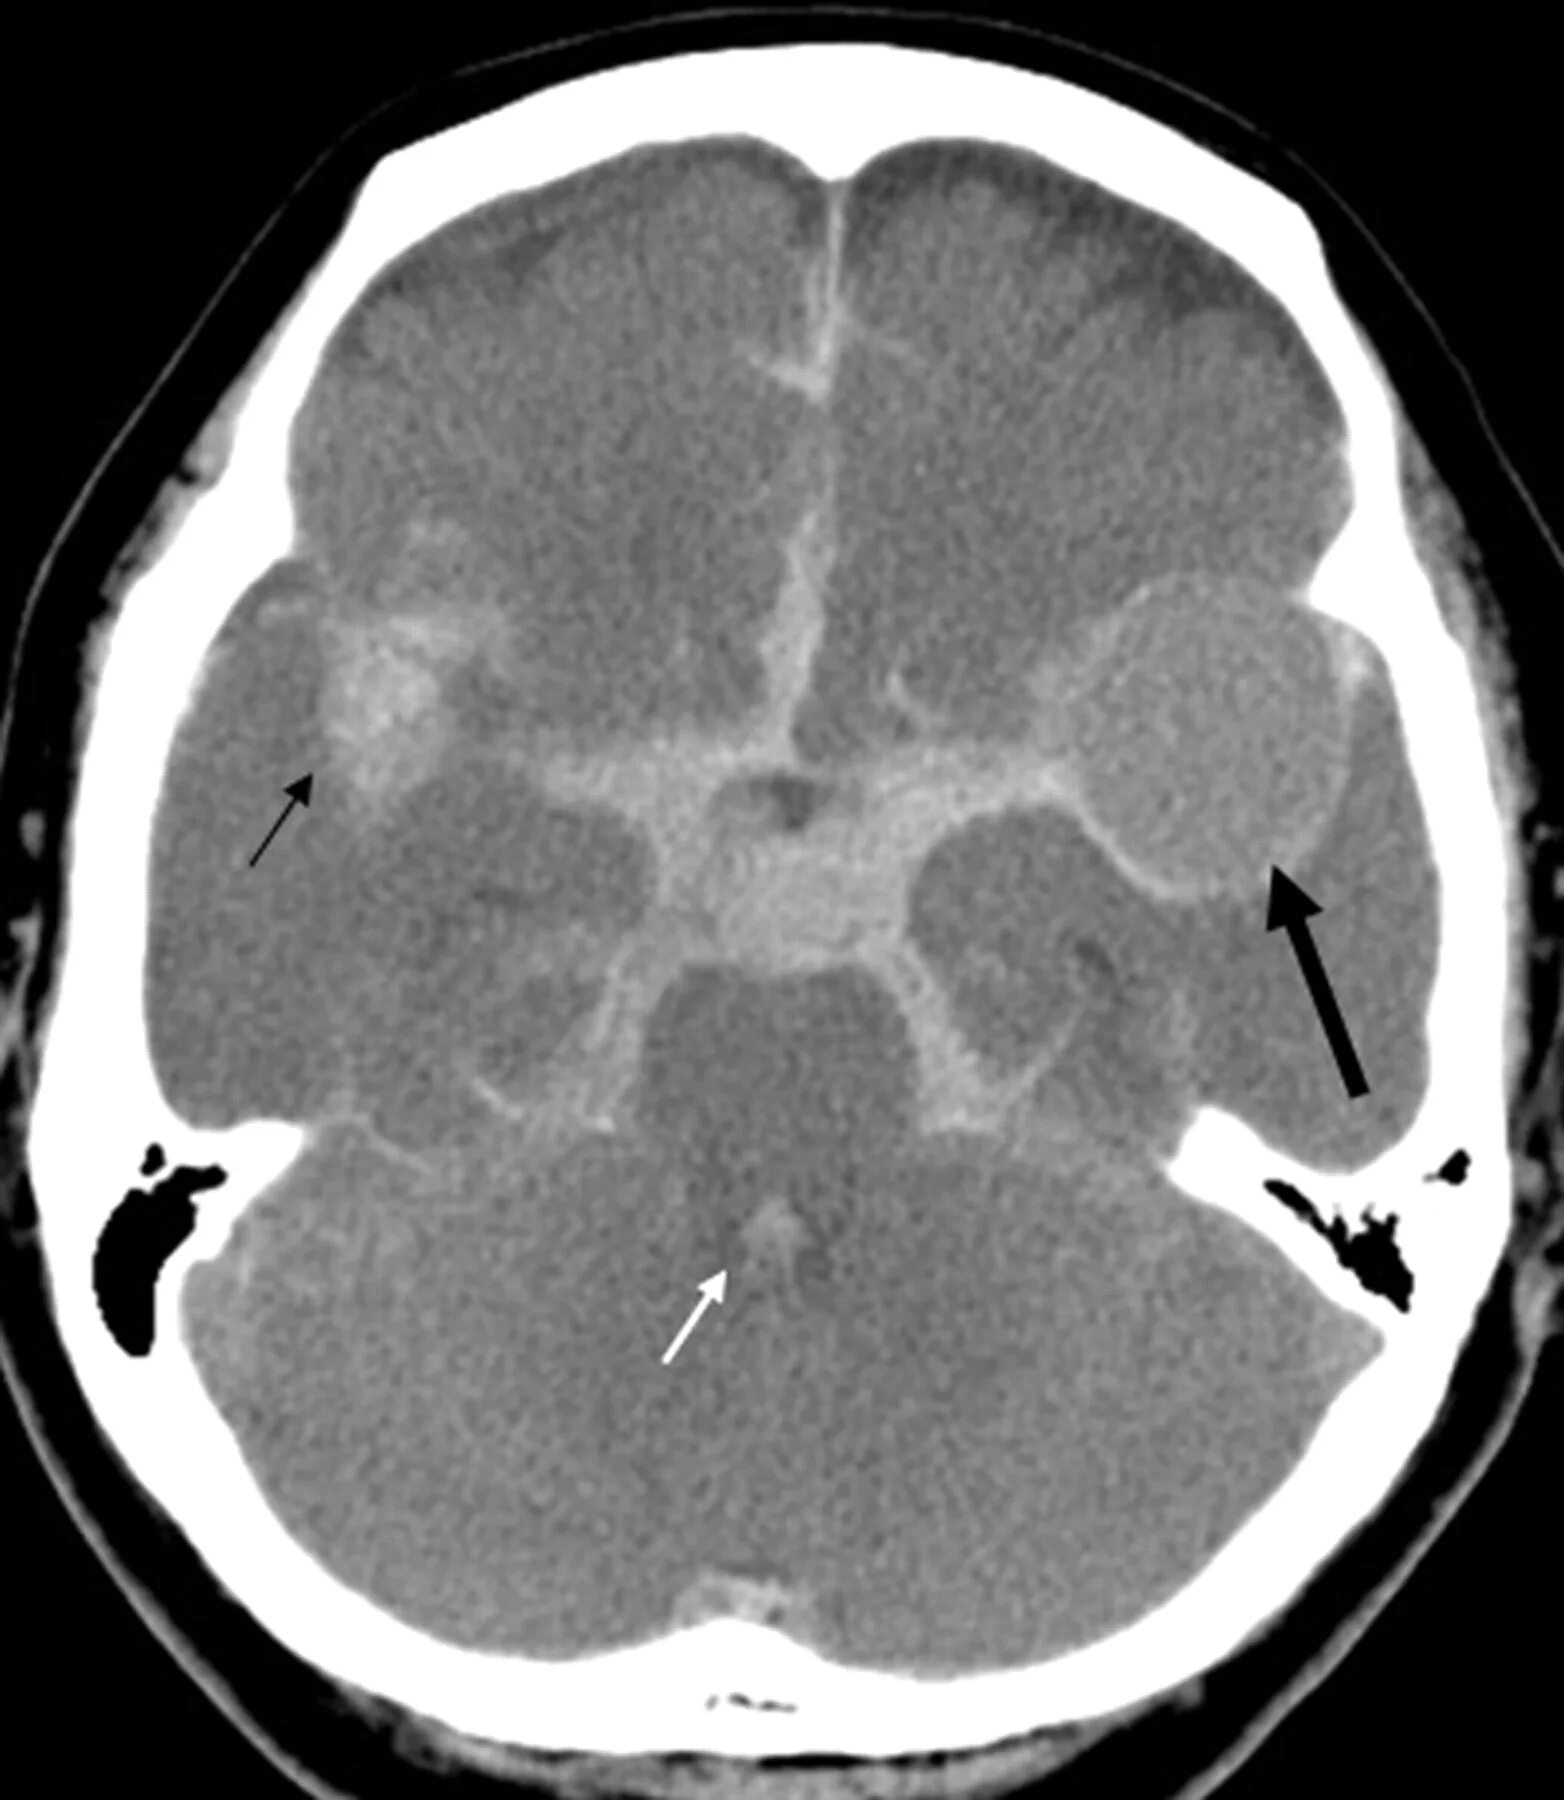

Цистерны на кт